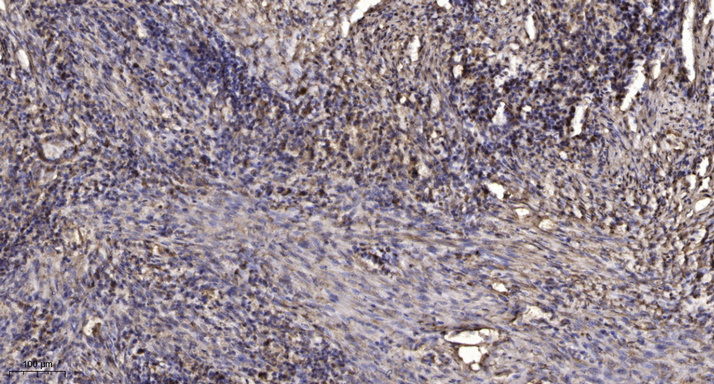

IHC (Immunohistochemistry)

(Immunohistochemical analysis of paraffin-embedded human Squamous cell carcinoma of lung. 1, Antibody was diluted at 1:200(4 degree overnight). 2, Tris-EDTA,pH9.0 was used for antigen retrieval. 3,Secondary antibody was diluted at 1:200(room temperature, 45min).)